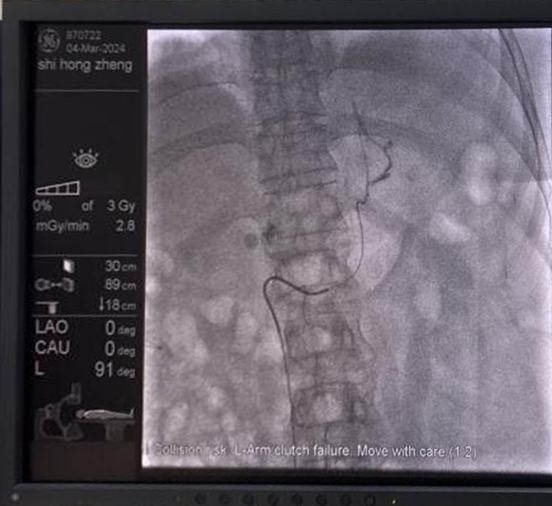

为了解决这个问题,昆山市中医医院MDT团队的血管外科团队亮相,对孙女士进行了双侧肾上腺采血术(AVS),检测了激素分泌情况,终于明确了左侧肾上腺为优势侧,诊断为醛固酮瘤,正是孙女士高血压、低血钾的元凶。

图片